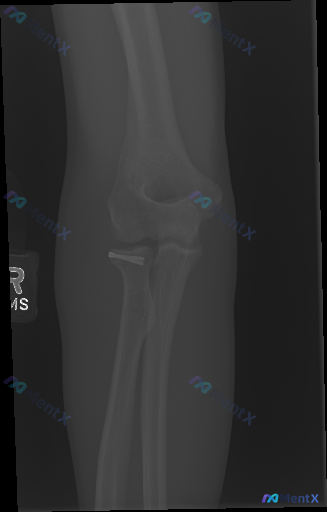

看到一张右侧肘关节侧位X光片,这个核心异常第一眼容易漏评估

整理到一张右侧肘关节侧位X光片的读片资料,先不说结论,大家第一眼会先注意到什么异常? 另外补充一个场景:如果这张影像的患者主诉是「近期肘关节疼痛/活动受限」,你的第一优先排查方向会是什么?